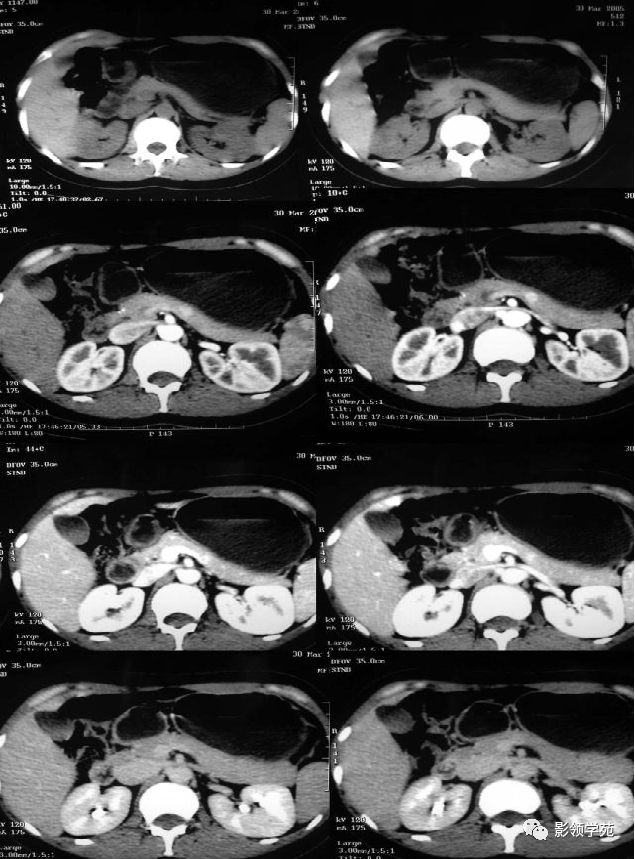

非功能性胰岛细胞瘤

图片尺寸540x658